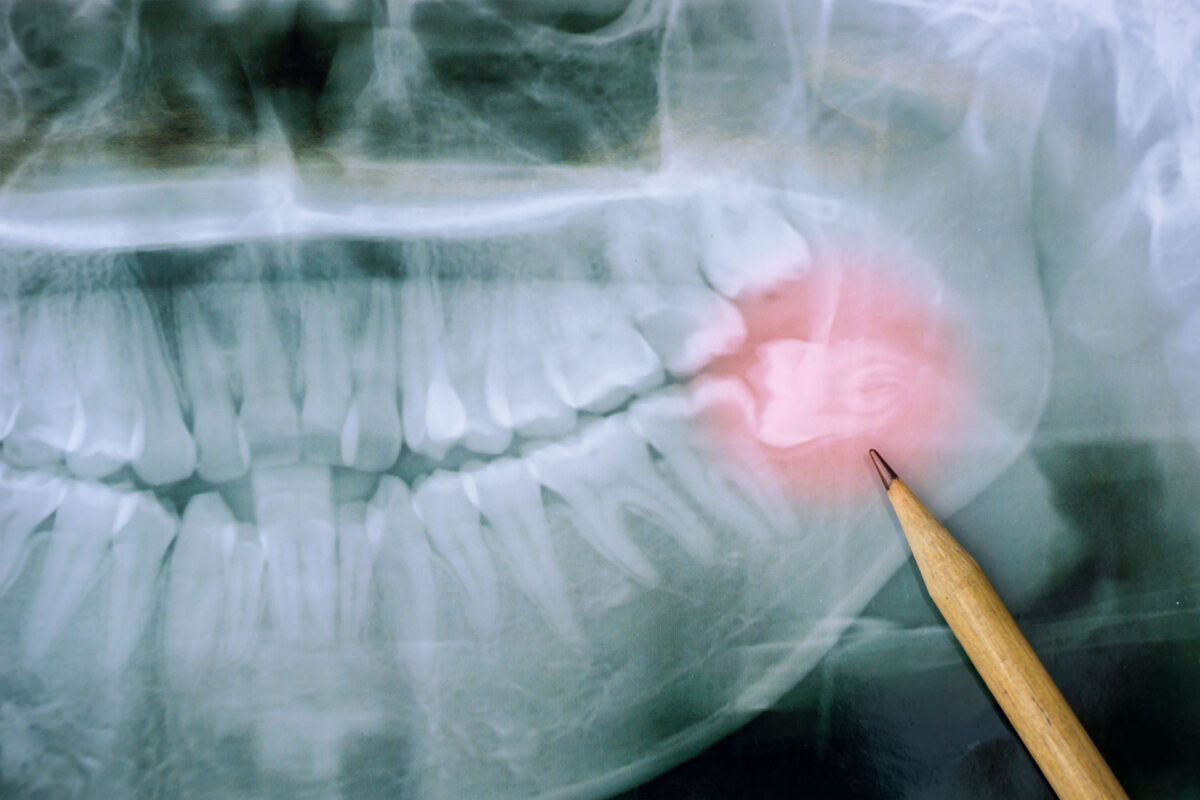

Les dents de sagesse

Les dents de sagesse Les dents de sagesse, ces dernières molaires qui apparaissent généralement à l'âge adulte, peuvent souvent poser problème. Au Centre dentaire Nathalie Giguère, nous rencontrons fréquemment des patients incertains quant à la nécessité d'extraire ces dents. Voici quelques éléments clés pour comprendre quand une extraction est nécessaire.